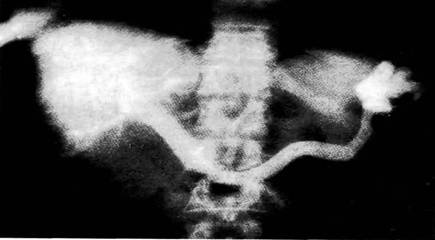

3. назовите метод и диагностический ризнак

4. назовите примененный способ и опишите его